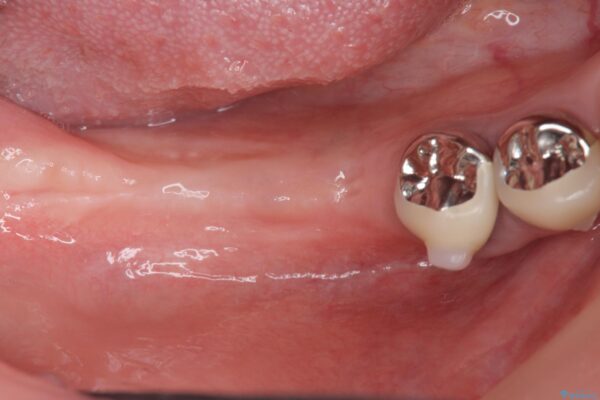

また、機能後のインプラント周囲の清掃性を高めるため遊離歯肉移植術を行っています。

インプラント周囲に強固な歯ぐきを移植することで、歯ブラシがしやすくなりインプラント周囲炎対策となります。